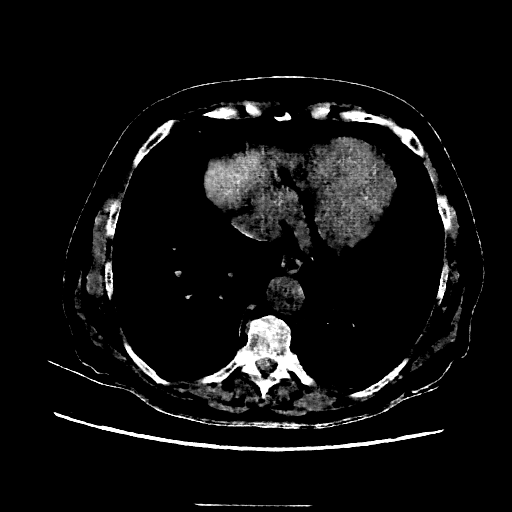

Image Grid

4Γ—3 grid: Rows show different image types (Original NATIVE, Reconstructed NATIVE, Original VENOUS, Generated VENOUS), Columns show windowing techniques (No Window, Lung Window, Mediastinum Window)

Mediastinum window (WL 40, WW 400 β†’ Low βˆ’160, High +240)

Original NATIVE CT scan (input)

Reconstructed NATIVE CT scan (cycle consistency)

Original VENOUS CT scan

Generated VENOUS CT scan (A→B translation)

Windowing Parameters